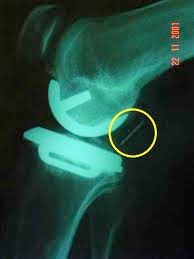

1. 1.Meniscal Bearing dislocation (0-3% quoted)

(see x-ray on the right)

Complication: X-Ray demonstrating a dislocated meniscal bearing in a uni-compartmental knee replacement

The yellow circle  above highlights the plastic meniscal bearing which has dislocated. It is normally located between the 2 metal components as seen below.